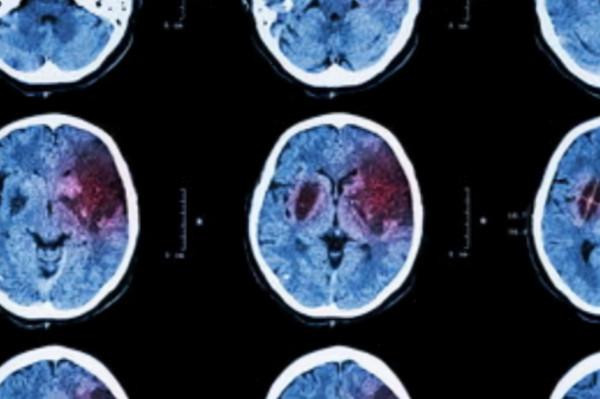

5. 出血頻繁。高血壓會引起動脈粥樣硬化,腦血管出血的現象。同時75-80%的患者會伴有其他身體器官出血的情況。因此高血壓疾病與心,肝,腎和身體組織息息相關。